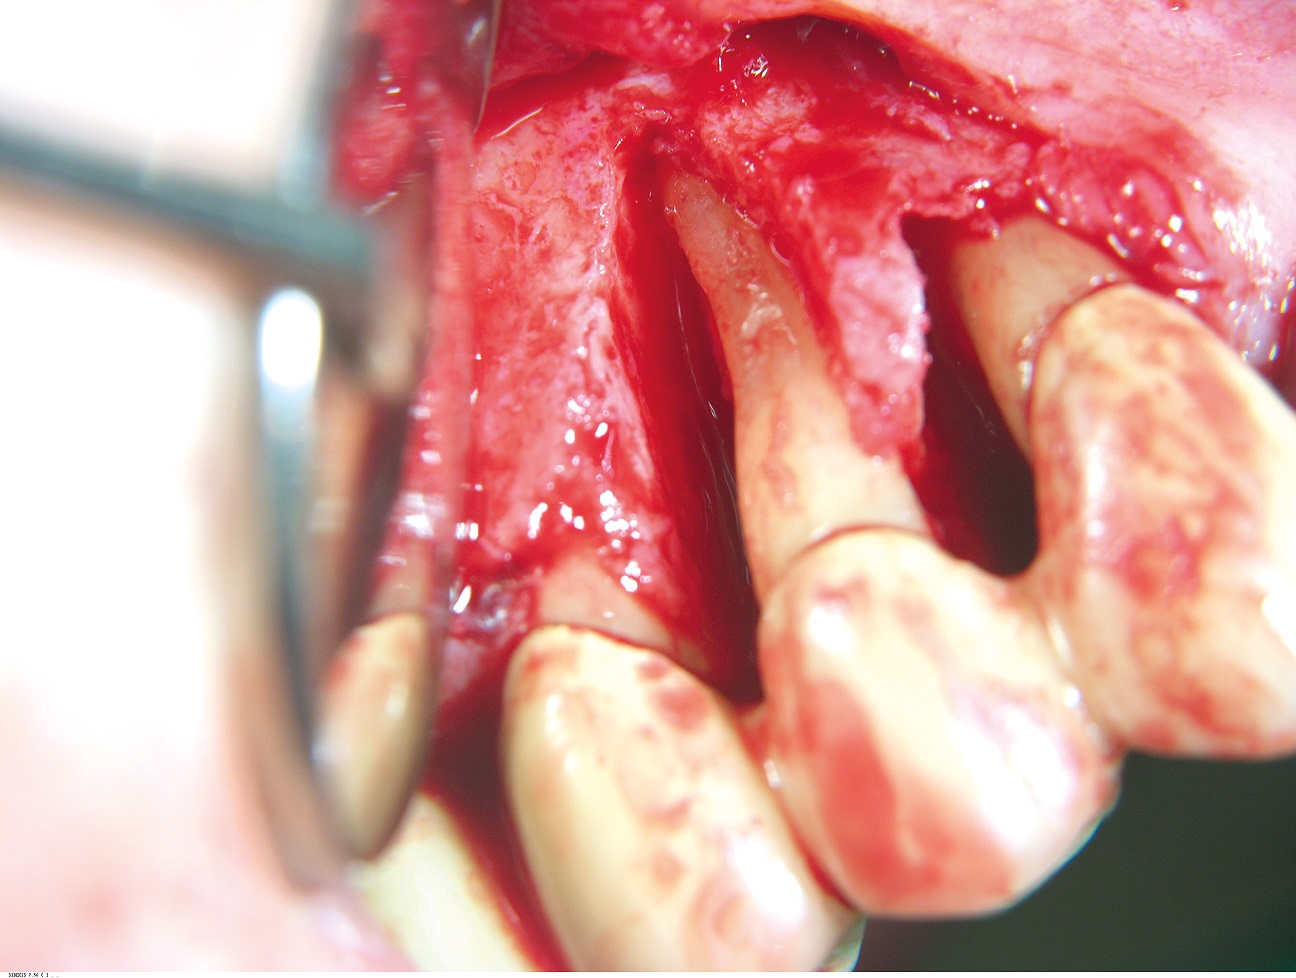

03/10 - Deep non-contained intrabony defect with a vertical bone loss of 12mm.GTR for the treatment of a deep three-dimensional intrabony defect using cerabone®, collprotect® membrane and Straumann® Emdogain® - Dr. T. Schwaar